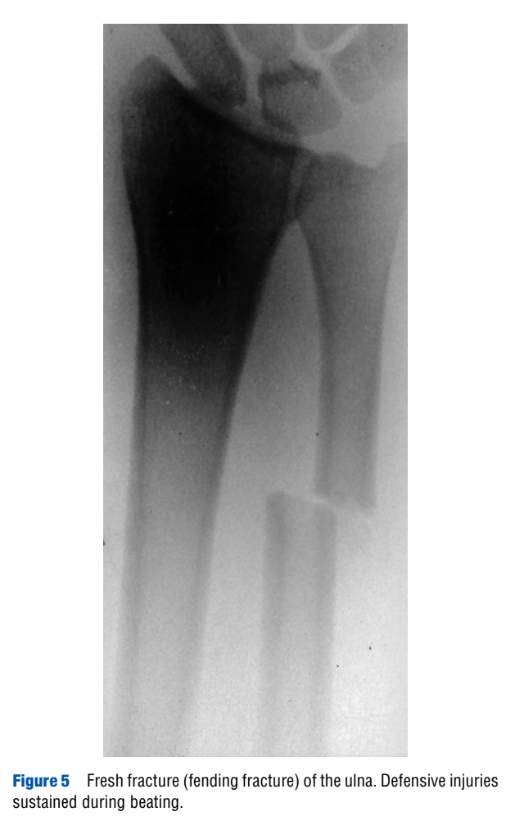

“Torture,” by H. Vogel. Encyclopedia of Forensic Sciences, second edition. 2013.